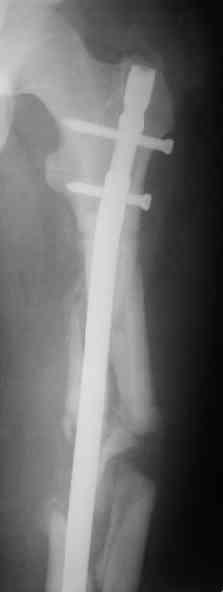

СМ> Если имеются под рукой Р-снимки, продемонстрируйте, плиз.

Вот несколько. С тисками и трубой на днях сделаем.

Саша, последний штифт, пожалуй, перегнули?

> Саша, последний штифт, пожалуй перегнули?

Там заход сделан как для прямого штифта, не через вертел.